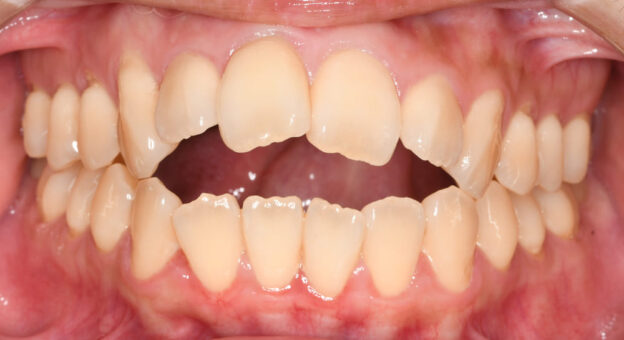

正面の口腔内写真では、前歯部の上下的な開き(開咬)が約10mmあり、通常の平均値(オーバーバイト:マイナス2〜3mm)と比べてかなり大きく開いている状態です。

正面の口腔内写真では、矯正治療のみで重度の開咬が改善され、前歯部の上下的な重なりも平均的なオーバーバイト(2〜3mm)へと回復しました。

右側の写真でも、前歯部の唇側傾斜(出っ歯)の改善と安定した咬合関係が得られています。

また、前歯部の後退により口唇閉鎖不全も解消され、自然な口元となりました。